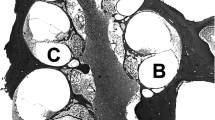

The estimated region of electrode B was selected as the region for histological analysis to ensure that we analyzed the cochlea in a region that was directly adjacent to the electrode array. Before removing the cochlear implant, a small notch in the bone was made with a needle to indicate where electrode B was located. Two implants (animals 335 and 361) were accidentally removed during the ear extraction process so their B location was estimated and based on the average distance from the round window to the B electrode for the subjects with intact implants. The implanted cochleae were removed, and tissue processing was performed as previously described (Yagi et al. 2000) and then modified as described below. Each cochlea was locally perfused with the glutaraldehyde and cacodylate buffer solution and placed in 3% ethylenediaminetetraacetic acid (EDTA) solution to decalcify until sufficiently soft for sectioning (approximately 1–2 months). Once decalcified, the implant was removed, and the cochlea was embedded in JB-4 resin (Electron Microscopy Scientific, Washington, PA, USA). Sections were obtained in the para-midmodiolar plane (Kanzaki et al. 2002) and were centered at the location of the notch in the bone that indicated the location of electrode B. These para-midmodiolar sections provided six measurable profiles of Rosenthal’s canal (Fig. 2). Sections were cut at a thickness of 3 μm, and 40 sections were obtained and collected on glass slides, covering a length of 120 μm along the cochlea spiral. The sections were stained with 1% toluidine blue in 1% sodium borate.

Light micrograph of a para-midmodiolar section from animal 350 showing areas of histological analysis. The letter designations are in the scala vestibuli, where resin from the sectioning procedure remains in most profiles and in scala tympani in profile “c”. While an imperfect section, it includes the entire cochlea showing regions that were analyzed and those that were not. Profile “a” represented the basal-most profile where the hair cells and neural elements were adjacent to the electrode array. Fibrous tissue remains in the scala tympani in profile “a” where the implant resided. Scale bar (upper left) represents 80 μm.

We sought to analyze regions of the cochlea adjacent to as well as apical to the electrode array. Thus, we analyzed four profiles of the cochlea and labeled them a, b, c, and d, starting from the basal end of the cochlea (Fig. 2). Profile “a” was the region upon which the para-midmodiolar sections were centered and represents the approximated region occupied by electrode B. Profile “a” is distinct from the remaining three profiles, as profile “a” was the only region analyzed that was adjacent to the electrode array. In contrast, the remaining three profiles (profiles b, c, and d) were apical to the electrode array. Regions apical to profile “d” were difficult to analyze because Rosenthal’s canal was not well defined. For the remainder of the manuscript, we consider profile “a” to be synonymous with the analyzed region of the cochlea that was adjacent to the electrode array, specifically the 120-μm region that was centered on the approximated location of electrode B.